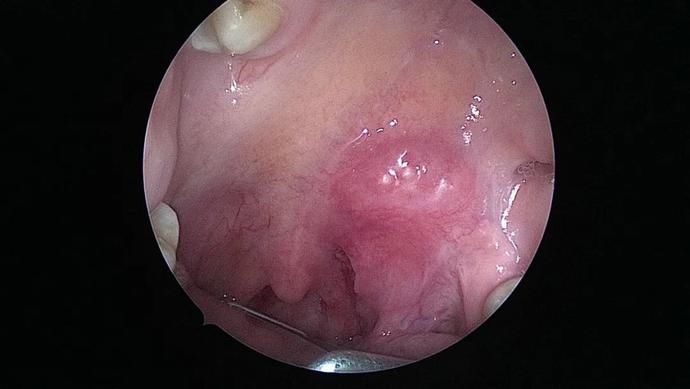

术前内镜见

文章插图